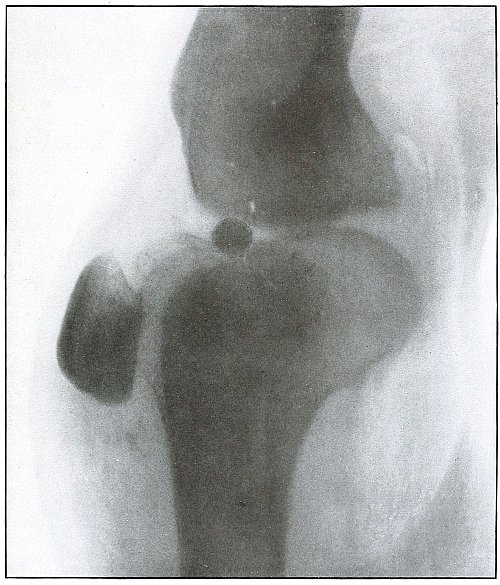

| 128.[Pg 6] |

Gunshot wound, knee |

266 |

| 129. |

Gunshot wound, knee |

268 |

| 130. |

Gunshot wound, knee |

270 |

| 131. |

Gunshot wound, knee |

272 |

| 132. |

Gunshot wound, knee |

274 |

| 133. |

Gunshot wound, knee |

276 |

| 134. |

Gunshot wound, knee |

278 |